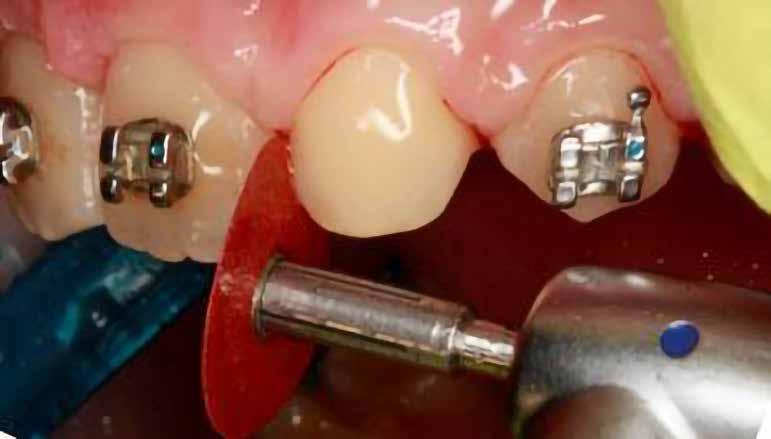

Szemfog becsiszolás

A szemfog elcsiszolásához piros gyémántfúró javasolt, finom szemcsézettséggel, 27-76 µm (okkluzálisan lekerekített – Rodentica, speciális hegyű 806314466514031, Komet 8833), gyorsítóval (max 160 000 fordulat/perc) megfelelő hűtés mellett, legalább 50 ml/perc. Ezt követi a felület kidolgozása és polírozása sárga gyémántcsiszolóval, extra finom szemcsézettséggel, 10-36 µm (Rodentica 806314466504031) és narancssárga Sof-Lex korongokkal (finom alumínium-oxid szemcsék 3-40 µm, extra finom, narancssárga-sárga, alumínium-oxid kristályok mérete 1,7 µm) könyökdarabban (25000 fordulat/perc) megfelelő hűtés mellett min. 50 ml/perc (2. a-d. ábra).

A szemfog megfelelő inklinációjának eléréséhez az oldalsó metsző helyén a palatinális felszínt is el kell csiszolni. Ennek a felületnek nem szabad interferenciát okoznia a harapásban, és lehetővé kell tennie a megfelelő metszőfog-vezetést [14]. A formázás előtt meg kell vizsgálni a szemfog vesztibulo-orális pozícióját. Lapos vesztibuláris felszínnel rendelkező szemfog esetén szükség lehet egy elsőrendű hajlításra a középső metsző és szemfog között (főleg, ha a szemfogon egy oldalsó metsző bracket van, melyben a beépített in-out érték magasabb) annak érdekében, hogy elérjük a megfelelő vesztibulo-orális pozíciót a fognyak szintjén, és elkerüljük a palatinális elcsiszolást (3. a-b ábra), [39].

Abban az esetben, ha a szemfognak kifejezettebb a központi lóbusa, a palatinális felszínről is el kell csiszolni, nem csak a vesztibuláris felszínről [40, 41]. A vesztibuláris felszín kifejezett elcsiszolása esetén ez már a dentint is érintheti, ami megnehezíti az esztétikai helyreállítást (a sárga dentin átüthet és a ragasztás is nehezebb ehhez a felülethez). Ezért a vesztibulárisan domború szemfogakat javasolt palatinálisabban pozicionálni, ami – együtt

2. a–d ábrák

a nagyobb mértékű palatinális elcsiszolással – lehetővé teszi a felépítmény kiterjesztését a vesztibuláris felszínen és a központi lóbus álcázását [39].

A zománc elcsiszolásának mértékét az orális és incizális felszínen a harapás határozza meg, ennek vizsgálatához tükröt és artikulációs papírt használunk [36]. Ideálisan, teljes interkuszpidációban a frontális kontakt olyan enyhe, hogy az artikulációs papír kicsúszik, míg propulzióban, metsző fogvezetésnél a jelölésnek a palatinális felszín incizális harmadában kell lennie mind a középső metszőn, mind a szemfogon. A gyémánteszközök legalkalmasabb formája a palatinális elcsiszoláshoz a lándzsa és rögbi alakú (Komet 0640, piros finom lándzsa Rodentica 806314257514020 (max. 300 000 fordulat/perc), rögbi Rodentica 800314278514020 finom piros (27-76 µm) gyorsítóban. Ezt követően könyökdarabba fogott Sof-Lex korongokkal szükséges polírozni (4. a-b. ábra).

A javasolt eszközhasználati sorrend a következő: piros gyémántfúró (finom 27-76 µm), sárga gyémántcsiszoló (extra finom, 10-36 µm) gyorsítóban megfelelő hűtéssel (5,6 ábra.). Alkalmazhatunk gyémántkorongokat vagy oszcilláló mozgásokat végző korongokat is. A polírozást Sof-Lex korongokkal vitelezzük ki (finom-narancssárga 3-40 µm, extra finom – narancssárga-sárga, 1-7 µm), [43,33], (7. a-b ábra). Az approximális felszínek elcsiszolása több lépésben történik megfelelő vízhűtés alkalmazásával és helyi fluoridálással.

Kisőrlő becsiszolása

Ha a szemfog helyére mezializált kisőrlő intrúziójára nincs is szükség, a palatinális csücsök akkor is akadályozhatja a harapást és a szemfogvezetést [44]. Ezekben az esetekben elcsiszoljuk a palatinális csücsköt (8. a-b ábra) piros gyémántcsiszolóval (finom, 27-76 µm, éli formázóval – Rodentica speciális tűhegy 806314466514031, Komet 8833 vagy GD – lándzsa Rodentica 806314257514020, Komet 0640) gyorsítóban (max 160 000 fordulat/perc) vízhűtés mellett, min. 50 ml/perc [39]. Extra finom sárga gyémántcsiszolóval polírozunk, 10-36 µm szemcsézettséggel (sárga éli csiszoló Rodentica speciális tűhegyű 806314466504031, GD – sárga lándzsa alakú Rodentica 806314257504020) és narancs Sof-Lex korongokkal (3M finom, narancssárga-alumínium-oxid kristály 3-40 µm nagysággal, extra finom, narancssárga-sárga, 1-7 µm alumínium-oxid kristályokkal) könyökdarabban (25 000 fordulat/perc) legalább 50 ml/ min. hűtéssel. Az elcsiszolást több lépésben végezzük, és ezt helyi fluoridalkalmazás követheti.